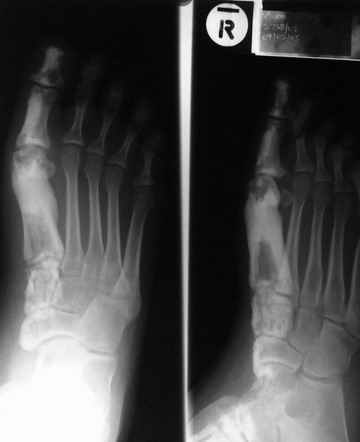

Кто шустрый - при какой патологии встречается так называемые "суставы Шарко"?Второе приобретение доктора Эмануэла мне понравилось своим романтическим названием: Candle bone - <кость-в-виде-оплывающей-свечи> : Просто редкая патология:

VR>Второе приобретение доктора Эмануэла мне понравилось своим романтическим названием: Candle bone - <кость-в-виде-оплывающей-свечи> : Просто редкая патология:

Остеосклероз при этом заболевании захватывает не всю кость по окружности, а простирается слегка волнистой

полосой вдоль длинной оси конечности (рис. 223, К), переходя через линию суставов на другие кости. Таким образом,

может оказаться пораженной целая верхняя или нижняя конечность или больший или меньший ее периферический участок,

например, часть лопатки, полуцилиндр плечевой кости, часть цилиндра лучевой кости и скелет II пальца вместе с

лежащими по этой оси участками запястных костей или же часть - медиальная или латеральная - бедренной,

болынеберцовой кости с продолжением и расширением процесса на предплюсневые и плюсневые кости и соответствующие

по длиннику фаланги одного или нескольких, но никогда не всех пальцев. Описавшие эту болезнь в 1922 г. Жоани

(Joanny) и Лери (Leri) сравнивают остеосклеротические полосы с картиной, напоминающей стекающий со свечи и

застывающий стеарин или воск, отсюда и название "мелореостоз" - "стекающая вдоль конечности кость".

Наконец, важным внешним клиническим выражением мелореостоза могут служить деформативные явления, из которых

раньше всего бросаются в глаза осевые уклонения в сторону одного из пальцев кисти.